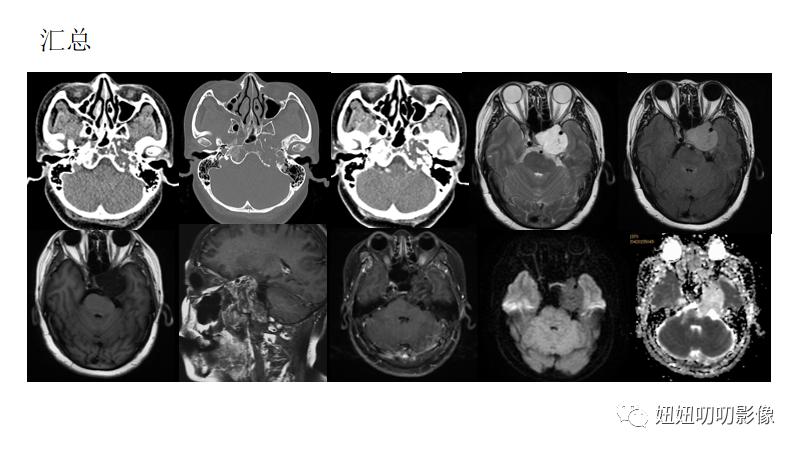

MRI:鞍区左侧见不规则形长T1长T2信号灶,其内见少许分隔,斜坡、海绵窦、颞骨岩部骨质破坏、吸收,边界欠清,大小3.6×3.7×4.4cm,DWI(b=1000)呈略高信号,ADC图未见明显异常低信号,增强扫描呈明显渐进性蜂窝状、颗粒状强化,脑桥前缘、垂体、垂体柄、视交叉、左侧颞叶受压移位,左侧颈内动脉、大脑中动脉受压、迂曲增宽。双侧额叶、顶叶皮层下、双侧放射冠区、双侧侧脑室旁区见多发斑点状、斑片状长T1长T2信号灶,边界尚清,T2-Flair呈高信号,DWI未见明显弥散受限。脑室形态未见明显异常。脑沟、脑裂未见明显增宽加深,中线结构未见明显移位。

MRI:鞍区占位性病变,考虑恶性肿瘤,软骨肉瘤或脊索瘤可能,请结合病理学检查。

①:病理:软骨肉瘤;

②:钙化典型,强化环形,T2巨亮,年龄中老年。